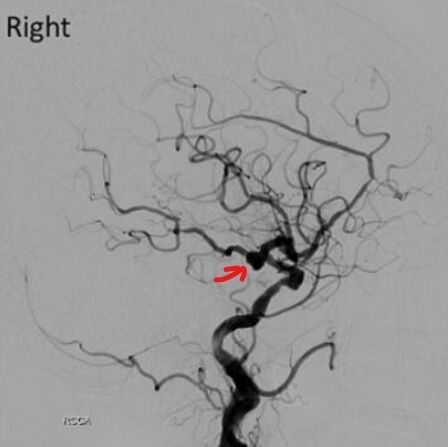

74.84歲女性,有高血壓病史,突然頭痛噁心而至急診求診。頭部電腦斷層檢查發現有廣泛蜘蛛網膜下腔出血 (subarachnoid hemorrhage, SAH)併腦室內出血;進一步做頭部血管攝影檢查,影像如附圖(右側及左側頸動脈造影),造成她SAH的原因最可能為下列何者?

(A)右側內頸動脈(ICA)和後交通動脈(PCommA)交界腦動脈瘤

(B)左側內頸動脈(ICA)和後交通動脈(PCommA)交界腦動脈瘤

(C)右側前大腦動脈瘤

(D)左側前大腦動脈瘤